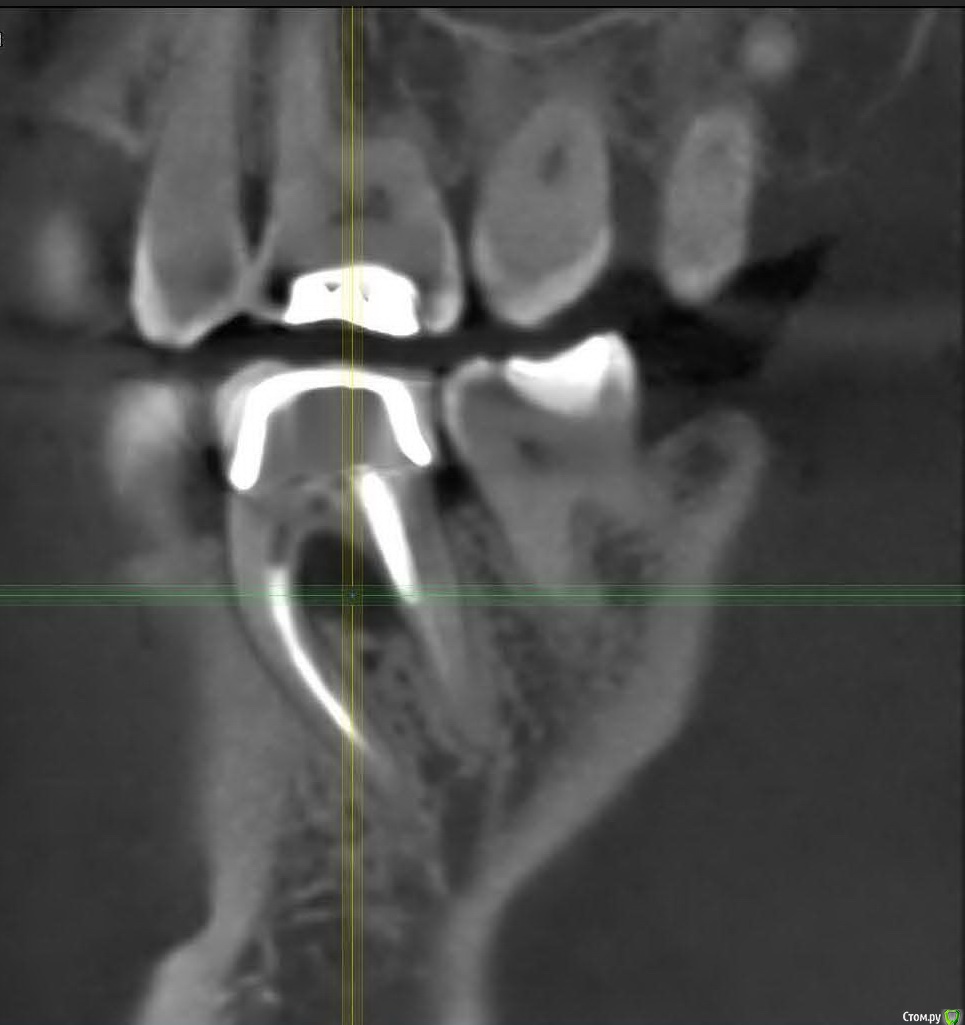

skyw Опубликовано 15 октября, 2017 Поделиться Опубликовано 15 октября, 2017 Прилагаю картинку зуба. Коронка стоит лет 12. Как я понимаю начался воспалительный процесс и уменьшение объема кости. Последние пару месяцев периодически воспаляется десна с внешней стороны этого зуба.Был у нескольких стоматологов - все говорят, что нужно удалять и ставить имплант. В том месте, которое я выбрал для проведения операции врач предлагает два варианта:1) удалять (с распилом зуба и удалением корней по отдельности чтобы максимально сохранить кость), если есть гнойный процесс, то все почистить\обработать, заполнить био-оссом разъеденный участок кости\лунки, зашить и через пару месяцев когда сформируется нормальная кость имплантироваться с установкой формирователя. 2) удалять с одномоментной имплантацией (в случае если какого-то нагноения серьезного там не окажется). Также с заполнением био-оссом пустот.Но при этом по центру имплант вкрутить как говорит врач не получится т.к. разрушится междукорневая перегородка. Т.е. имплант будет вкручиваться в зону одной из лунок (т.е. стоять не по центру, что как лично мне кажется несколько усложнит в дальнейшем установку коронки и понизит прочность конструкции под нагрузкой). Вопрос к специалистам - как считаете каким путем лучше пойти ? По поводу непосредственно импланта предлагаются два качественных с точки зрения врача варианта: бюджетно - Osstem, небюджетно - Astra Tech.Как считаете, остановится на Осстем в разрезе того, что цена зуба в итоге в два раза ниже чем с Астрой ? Или же эта экономия потом боком выйдет и лучше не рисковать ? Не хотелось бы через 10-15 лет чинить этот зуб опять.Врач говорит, что Астра приживается несколько быстрей, работать лично ему с ней удобнее и за счет микрорезьбы в районе шейки импланта меньше риск того, что кость с годами будет убывать в этой зоне. Особенно последний пункт меня заинтересовал. Ссылка на комментарий

skyw Опубликовано 15 октября, 2017 Автор Поделиться Опубликовано 15 октября, 2017 Вы могли бы на моей картинке нарисовать схематично позицию импланта при одномоментной установке как Вы это видите ? С учетом почти наполовину сгнившей перегородки не понимаю как его по центру зафиксировать. А устанавливать в одну из оставшихся от корня лунку как предлагает врач тоже не нравится идея - получится что имплант будет ближе к 5 или 7 зубу (совсем не по центру) и коронка соответственно также будет также асиметрично крепиться. Никаких сложностей с позиционированием импланта быть не должно,перегородка останется. Ставить лучше одномоментно и с формирователем десны. Наличие или отсутствие микрорезбы при одномоментной имплантации ,не сказывается на убыль кости в дальнейшем. Астра тек и осстем имеют аналогичное внутреннее коническое соединение. В вашем случае прекрасно и осстем сработает. Ссылка на комментарий

колесников Опубликовано 15 октября, 2017 Поделиться Опубликовано 15 октября, 2017 Срез некорректный. Вам не нужно понимать как будет все происходить,доверьтесь доктору. С биосом кость за 2 месяца не сформируется. 3 Ссылка на комментарий